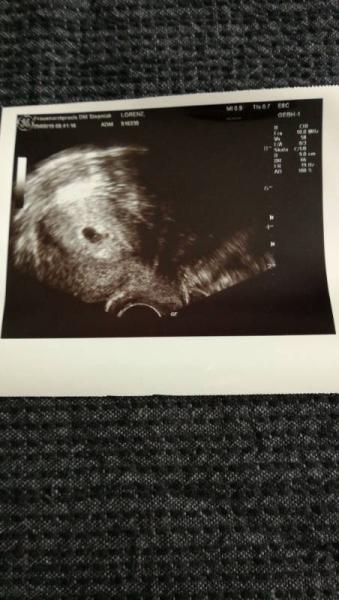

Guten Morgen. Ich bin laut meiner App jetzt bei ssw 6+5 letzte Woche war ich das 1.mal bei meiner fa man hat die fruchthöle gesehen mit einem kleinen weißen punkt darin. Sie konnte noch nicht genau sagen, wie weit ich bin. Nächsten donnerstag muss ich wieder hin zur großen Untersuchung und hoffe das ich da meinen Mutterpass bekomme. Mir ist den ganzen Tag extrem übel. Ich bekomme kaum was zu essen runter... Übergeben habe ich mich aber noch nicht(zum glück). Hat jemand einen Tipp gegen die Übelkeit?

Bild zu Starke Übelkeit - Forum für Januar - Mamis